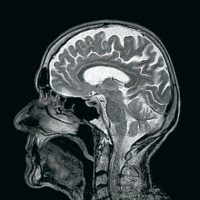

Органы: Береги мозг смолоду

У мозга, как и у других органов, есть свой биологический возраст, который не всегда соответствует календарному возрасту человека. Старость мозга — это разрушение связей между его клетками, нейронами. Американские и новозеландские ученые решили определить с помощью МРТ возраст мозга почти у 900 человек. Оказалось, что в группе испытуемых примерно одного возраста (45 лет) у кого-то был юный 24-летний мозг, а у кого-то — 70-летний. У людей с «пожилым» мозгом был сильнее выражен спад умственных способностей, и выглядели они значительно старше. Заглянув в старые медицинские записи добровольцев, ученые обнаружили, что предсказать скорость старения мозга можно очень-очень рано — уже в трехлетнем возрасте (а следовательно, можно заранее разработать меры профилактики). (4)